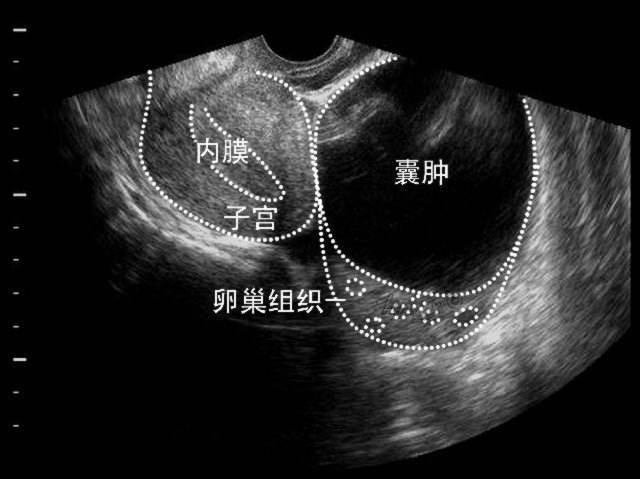

除卵巢囊肿隐患 奥洛克微电极技术显身手